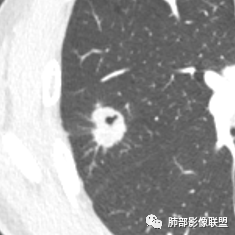

患者右上肺占位,内部强化不均,有空泡,有血管穿过,血管聚集现象,似有胸膜牵拉,考虑恶性

右肺上叶后段占位病灶,病灶不规则,周围胸膜线性牵拉,病灶部分周围有晕,病灶内见不规则空洞,未见明显引流支气管,长毛刺,多分叶、肿块边缘部分L型,可见血管直接供养。增强见点状坏死、病灶内血管。综上考虑恶性可能性大,鉴别隐球菌。

右肺上叶结节,浅分叶膨隆,边缘可见胸膜牵拉及血管集束,不规则厚壁空洞,不均匀强化,血管进入病灶,边缘毛燥,考虑低分化腺癌,鉴别隐球菌。

晨读:双肺胸膜下多发小气囊,大小不一,右肺结节,内部可见小空洞,洞壁光滑,厚薄不一,偏心性生长,近段血管束增粗,有分叶,毛刺(软),有晕征,平扫密度尚可,增强后不均匀强化,可见低密度坏死,及部分血管穿行,体检发现,考虑恶性:腺癌,鉴别炎性结节

右上叶结节,轻分叶,结节有长短不一毛刺,结节周围GGO边界清,有血管集束征,肺窗结节周围似可见卫星灶,可见鬼脸征,良恶性征象都有,但GGO边界清,浸润性腺癌耍考虑,临床症状轻微,体捡发现,似可见卫星灶和鬼脸征,炎性肉芽肿TB或隐球菌要鉴别。

有空泡征,实性部分密度均匀?强化均匀?

内部血管怎么样?

支气管?

我觉得搞清楚空洞还是空泡也很重要,空泡指向癌,空洞癌、结核、PC都可以

就这一例而言我也不知道是空泡还是空洞,感觉不具有形成空洞的病理基础(坏死物经支气管排出);所以一开始就请教老师了